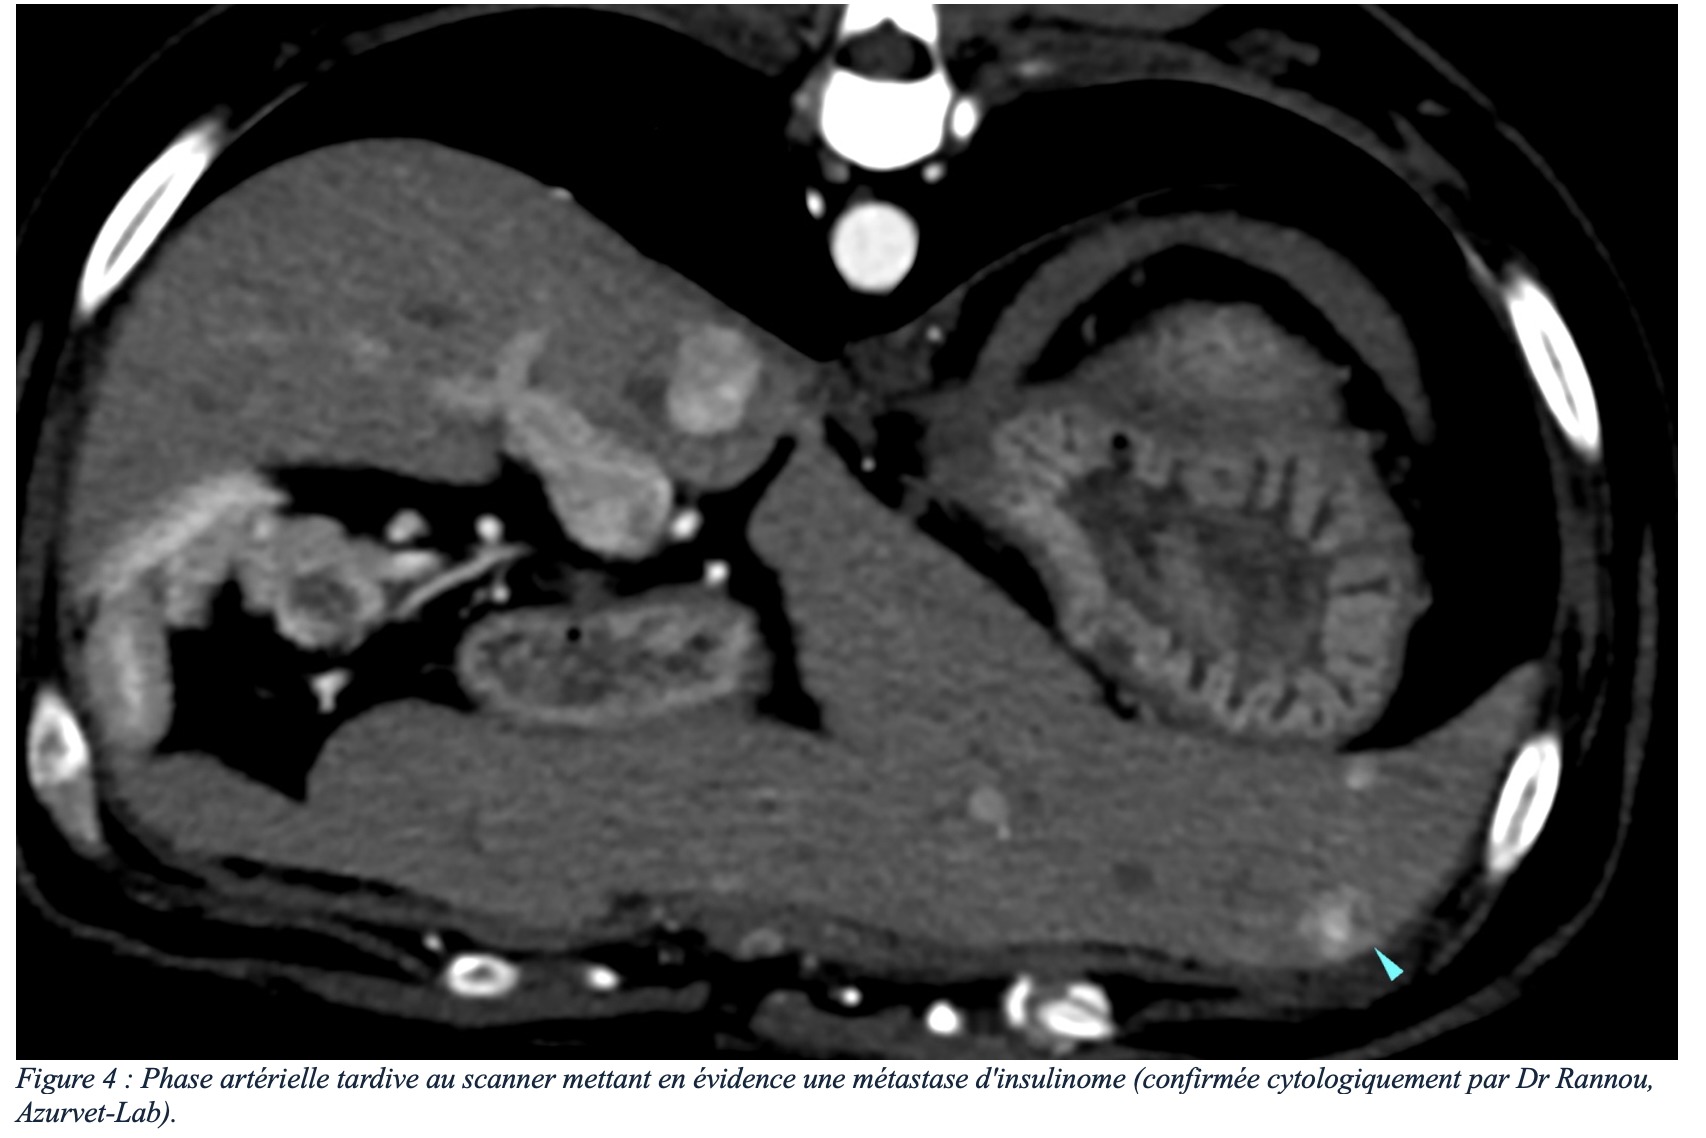

L’importance de l’imagerie lors d’insulinome

L’insulinome est une tumeur neuro-endocrine peu fréquente, rencontrée chez le chien et le furet et de façon beaucoup plus rare chez le chat. Les signes…